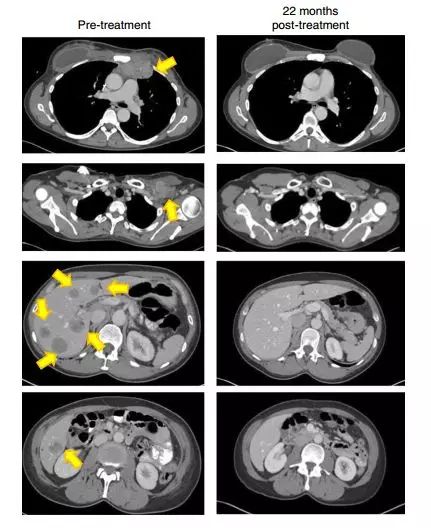

免疫治疗结果喜人! 研究论文文献的作者也是NCI癌症研究中心的外科主任Steven A. Rosenberg教授,Rosenberg教授说:“一旦癌症发生了转移,大多数患者将面临的是死亡,因为对于转移性的肿瘤,我们一直没有找到有效的治疗方法。” 研究人员找到这名乳腺癌患者的时候,49岁的她已经被乳腺癌反复折磨,尝试过化疗和内分泌治疗等,但是这依然没有延缓肿瘤的进展和转移。这名几乎被判了死刑,可能仅有几个月生命的患者,决定参加这项细胞疗法的临床试验。 研究人员先在肿瘤里面找到肿瘤浸润性T细胞(TILs-一种可以识别肿瘤特异性的抗原),然后把它们从肿瘤中分离出来,在体外分析。虽然分析结果并不如预期,在62中突变中仅有4种被T细胞识别出来,而且这类T细胞数量也非常小。于是研究人员把这些有用的T细胞扩增制造出900亿个细胞,再返回到患者体内。 不仅如此,在肿瘤浸润淋巴细胞正在生长的同时,患者还接受PD-1阻断免疫治疗剂Keytruda的治疗,以修改免疫系统,使其他免疫细胞在被大量扩增后注入患者时不会干扰TILs。 于是,奇迹出现了!在6个月后的随访影像学检查中,患者所有肿瘤都消失了!(下图的左列是之前的影响学检查结果,右侧一列是之后的影像学结果。黄色箭头指的是肿瘤)不竟如此,22个月后,肿瘤依然没有复发! 免疫疗法要逆天! 不仅如此,研究人员还认为这种治疗对一些常见的上皮癌和他们的转移肿瘤都是有治疗潜力的。他们还成功治疗过其他三种不同类型的转移癌:结直肠癌、胆管癌和子宫颈癌。 “在未来,这种治疗方法可能应用于更多的癌种” Rosenberg教授说。特别是对于一些有转移的患者,因为他们可能由于之前的治疗,产生耐药性。或者转移灶拥有和原始肿瘤完全不一样的突变。 正如Rosenberg教授教授说的:“导致肿瘤发生的突变也可能成为可攻击的、肿瘤的致命弱点。” 那么新疗法的耐药性如何呢? 奇怪的是,研究人员发现与新的个性化治疗相比;老的化疗药物治疗下,由于采取的是地毯式轰炸破坏癌细胞和它们的基因组,这使得肿瘤细胞更难发展出抗性。 新的治疗方式可能只是针对一个或者很小数量的癌细胞突变蛋白组,这可能会使得肿瘤更容易产生耐药性。这个部分还需要更多的研究,从而来确认TILs可能的靶点。 免疫疗法的实用性 如此个性化的治疗,是不是很难大规模的推广和应用呢?不一定哦!如果进行大规模的试验,无疑是非常大的挑战,需要很大的实验室和专业知识。但是美国已经有公司开始进行冠以TIL疗法的试验了。 “我们正在将患者自身的淋巴母细胞发展成治疗,他们是天然的T细胞,而不是基因工程。这是你可以想象的最高度个性化的治疗,“ 罗森伯格说。